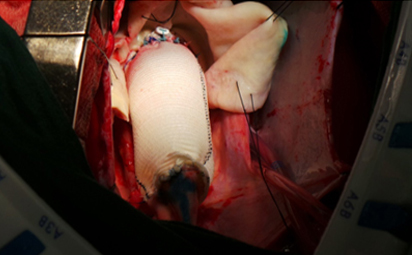

Aortic Aneurysm ( Dilated Ascending Aorta )

Replacement of Diseased Aorta with a Artificial Graft